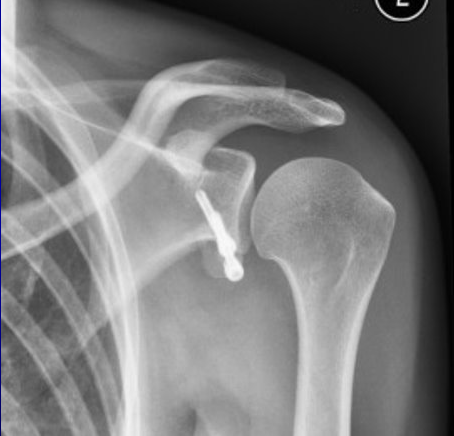

Lararjet(らたるじぇ)法の手術後レントゲンです

烏口突起移行術とは、共同腱のついた烏口突起をボルト(スクリュー)で関節窩に固定します。